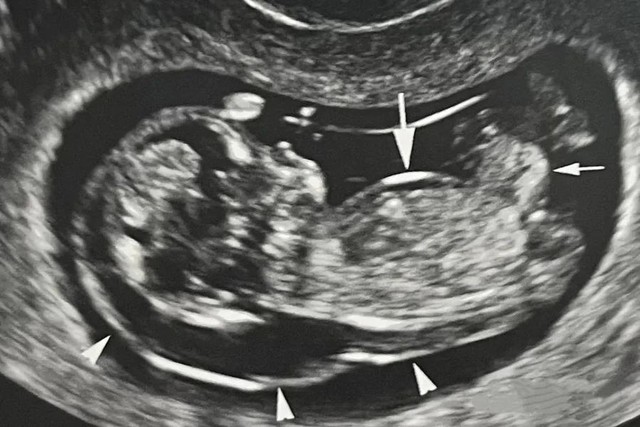

Top 4 dị tật bẩm sinh thường gặp ở trẻ sơ sinh và giải pháp phát hiện sớm từ trong bụng mẹ - Ảnh 1.

Hội chứng Down được sàng lọc thông qua siêu âm hình thái, đo độ mờ da gáy ở tuần thai 11 đến 13 tuần 6 ngày